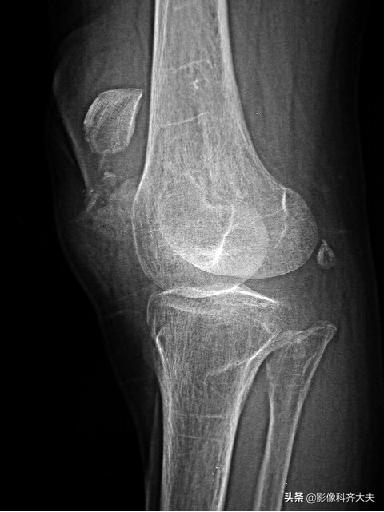

骨挫伤(bone bruise):外力作用引起的骨小梁断裂和骨髓水肿、出血,T1WI低信号,T2WI高信号,压脂序列显示清晰。平片和CT 上常无异常发现。

例:右胫骨骨挫伤

右胫骨骨挫伤-平片正常

右胫骨骨挫伤-CT正常

右胫骨骨挫伤-MRI清晰显示病灶位置

胫腓骨骨挫伤

胫腓骨对应性骨挫伤